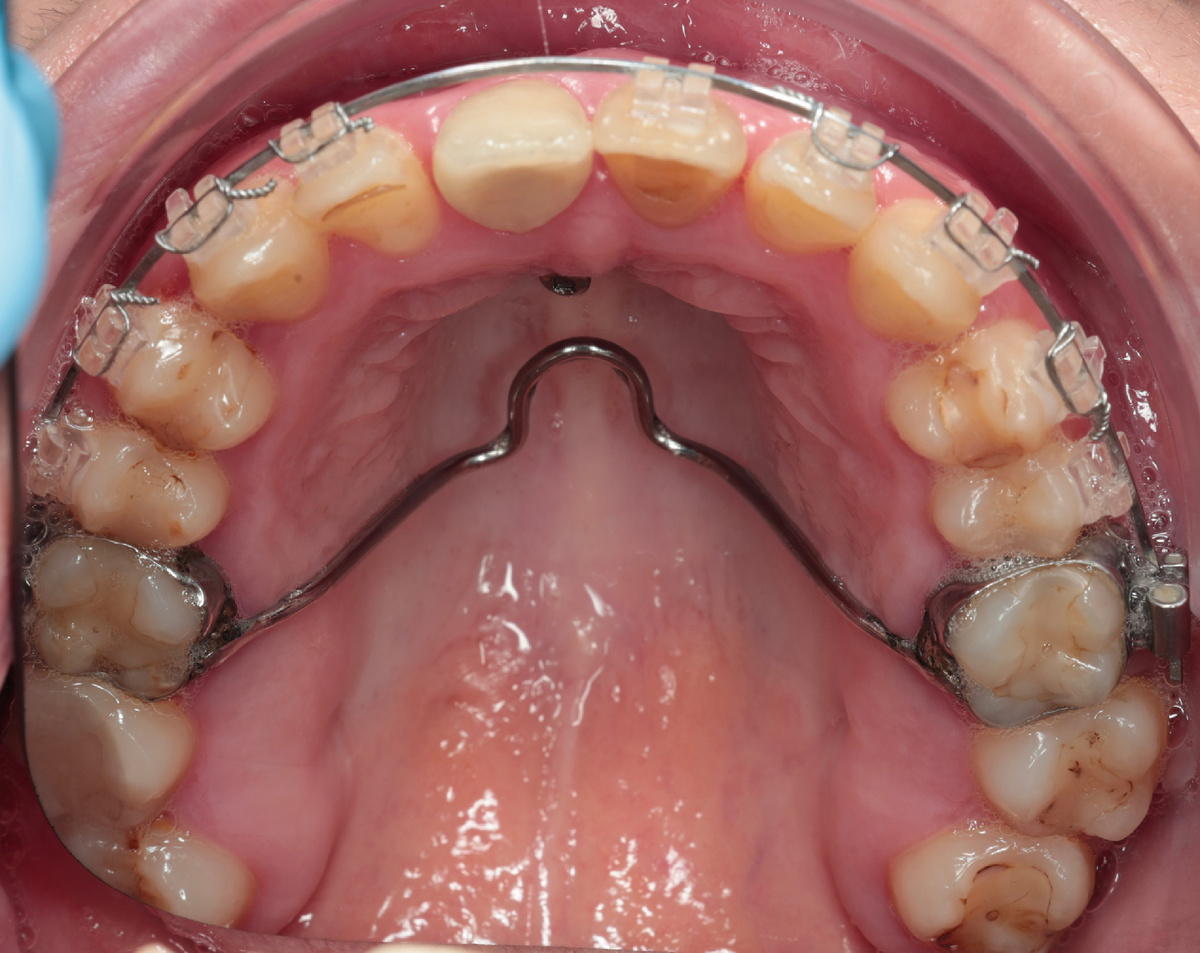

Весной 2025 она написала снова: - "Здравствуйте, я всё-таки надумала лечиться у вас". Пришла - всё с тем же расширителем на верхней челюсти, с остатками брекетов.

Мы провели полную диагностику. Ситуация непростая - кортикальная кость в значительной степени утрачена, часть нижних резцов подвижна, прикус не смыкается как нужно. Скелетный третий класс - нижняя челюсть выдвинута вперёд, плюс последствия многолетнего лечения, которое не было доведено до конца.

На фронтальных зубах нижней челюсти брекеты вообще не ставились - судя по всему, предыдущий специалист понимал, что ситуация нестабильна и не рисковал. Это само по себе говорит о многом.

Сняли брекет-систему: